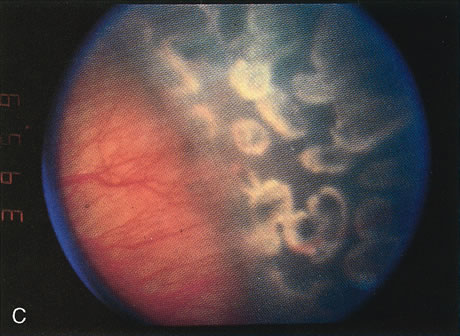

EXPECTED RESULTS

Several small prospective randomized trials have compared the efficacy of laser photocoagulation to cryotherapy for threshold ROP30,31,40,41 No statistically significant study has proven its efficacy, but they have suggested that laser treatment is as effective as cryotherapy in the treatment of threshold ROP (Fig. 6). A number of other studies have assessed the structural and functional outcomes following both argon and laser treatment of threshold ROP, with good results (Table 4).

Fig. 6. A. Peripheral neovascularization in zone I. B. Peripheral retina immediately after argon laser photo-coagulation. C. Peripheral retina 1 week after argon laser photocoagulation. D. Peripheral retina 1 month after argon laser photocoagulation. Note the complete regression of neovascularization.